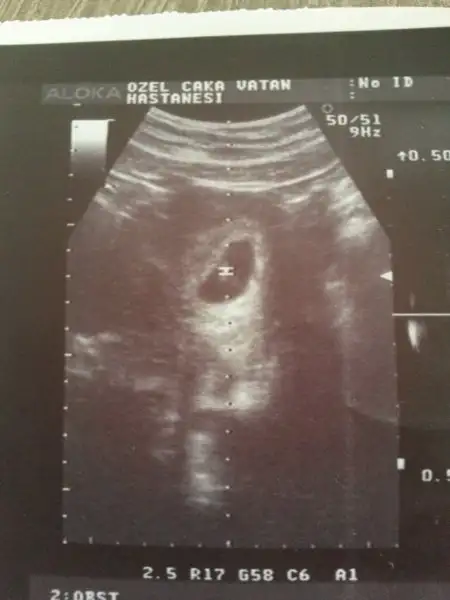

Eki Görüntüle 1707425 Eki Görüntüle 1707427 birde benim miniğime bakarmısınız hanımlar bu 7+4 günlük ultrason görüntüsü

vayyy terbiyesiz, öyle oyunlar yapmayı da öğrenmiş yani şimdiden, çok işim var benim diyosunuz :)Cnm senin bebek bizimle oynuyor:)ilk resimde solda ikinci resimde sağda o yüZden yorum yapmayacağım.sen 11 12 haftalık fotosunu atarsin ilerde o zaman nubuna bakarım.

Benim tahminim eğer karından bakıldıysa bu bebek kızEki Görüntüle 1707425 Eki Görüntüle 1707427 birde benim miniğime bakarmısınız hanımlar bu 7+4 günlük ultrason görüntüsü

sanki sola daha yakın gibi değilmi ? yani ben oğlum olsun çok istiyorum da :)Benim tahminim eğer karından bakıldıysa bu bebek kız

canım bana da sağa daha yakın gıbı geldi:) rabbim gönlündekini hakkında hayırlı eğlesin inşsanki sola daha yakın gibi değilmi ? yani ben oğlum olsun çok istiyorum da :)